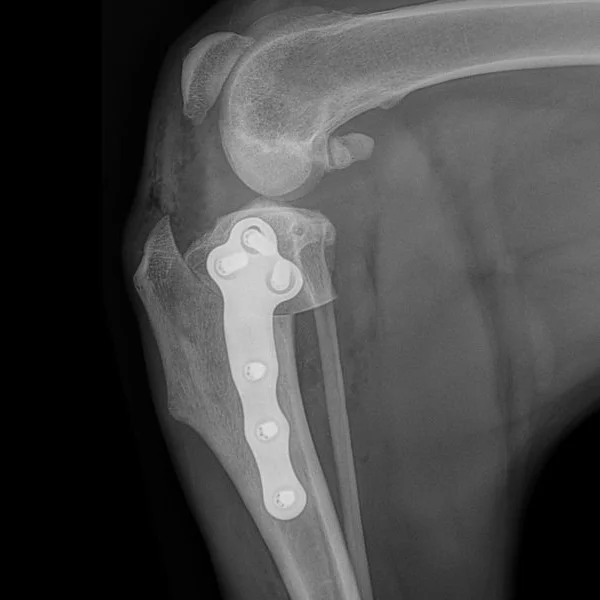

KYON ALPS® TPLO

The ALPS® TPLO system offers surgeons a simple, robust, biological, titanium solution for all patients requiring a TPLO surgery.

The ALPS® TPLO plate is an integral part of the ALPS® Product Range. The minimal contact design of the plate underside and preferred use of monocortical KLS™ screws minimize vascular damage,accelerate healing and reduce infection risk. KYON ALPS® TPLO gives surgeons advantages in and out of the operating room. The contoured shape and consistent locking mechanism make surgical application convenient and routine.

Eliminates intra-operative contouring. With eight sizes for toy to giant breeds, the novel plate shape is optimized to match the TPLO construct and anatomy.

Low profile and smooth transitions improve comfort beneath the skin, ideal for sensitive patients with minimal soft tissue cover.

Manufactured from titanium alloys for supreme biocompatibility and strength, plates have a  22% stronger construct strength than competitors’ stainless steel locking plates [1].

Compression across the osteotomy is optional, performed using a custom drill sleeve and designated compression hole.

KLS™, featuring a novel thread shape and locking mechanism, are used across the ALPS Product Range. KLS™ screws can be used bicortically or monocortically.